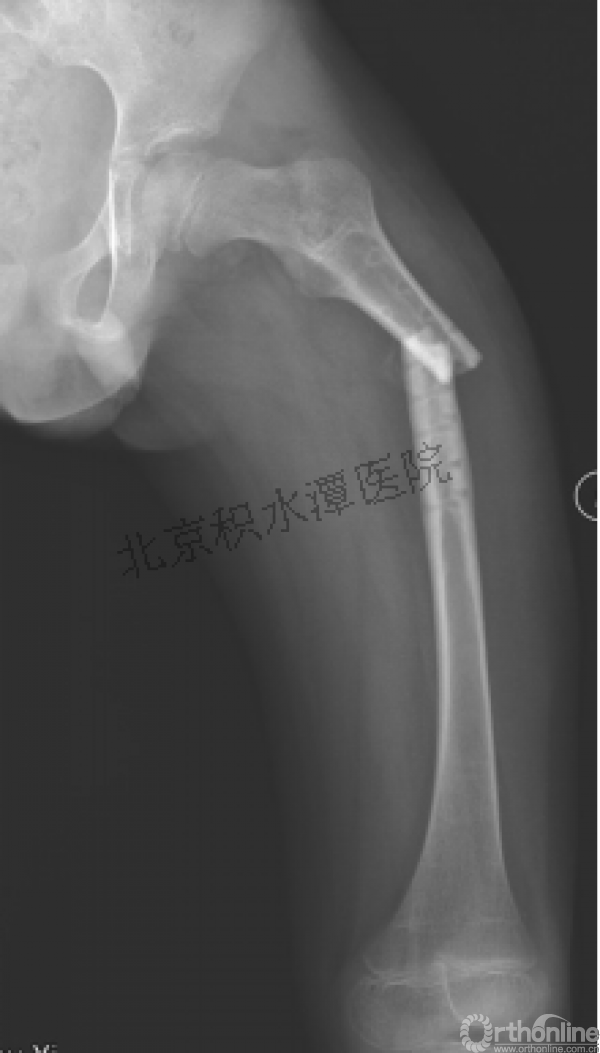

病例分享一

男孩 、5岁,初次骨折于2007年7月。